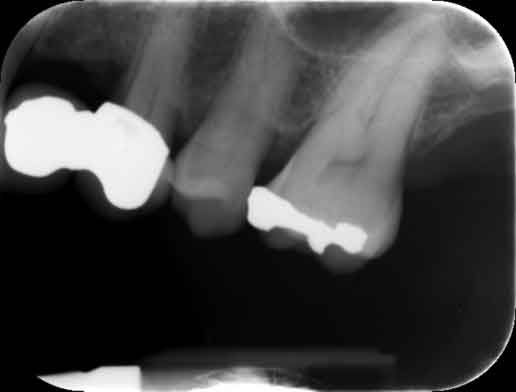

Return to "Modern Applications for The Cantilever Fixed Partial Denture" partial-denture-14b Next Previous